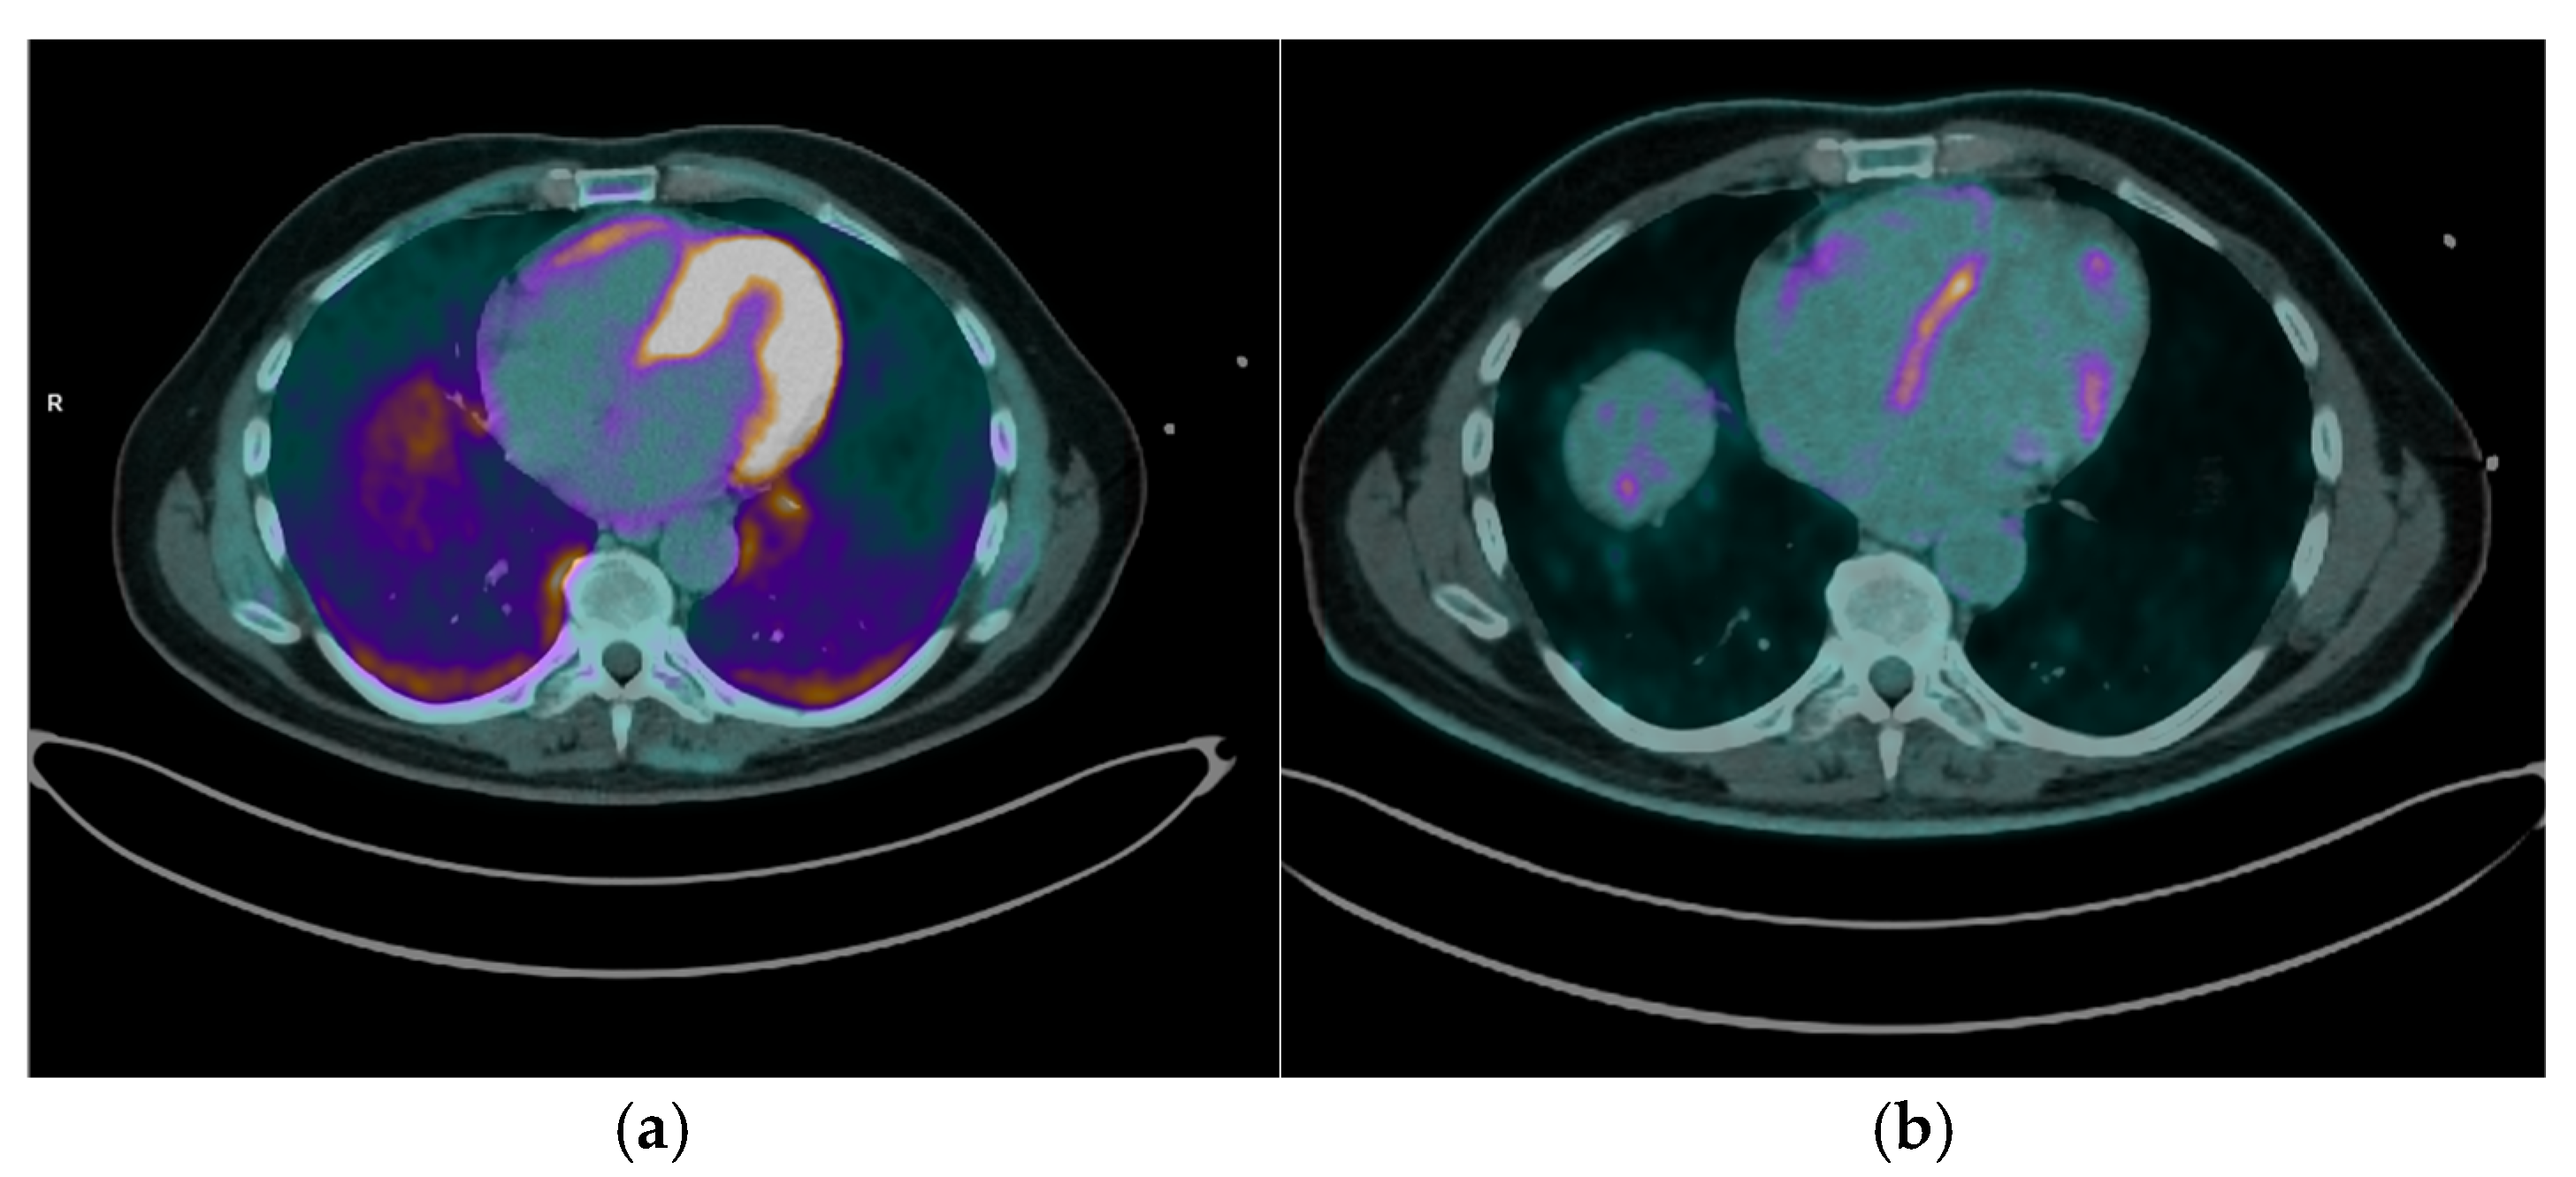

- The integration of perfusion imaging with 13N-NH3 PET/CT enhances the diagnostic and prognostic value of PET/CT. By distinguishing areas of perfusion defects (indicative of fibrosis) from regions of increased FDG uptake (active inflammation), clinicians can fully characterize the spectrum of disease, from isolated inflammation to fibrosis, and overlapping pathology, for comprehensive disease evaluation, prognosis, and guiding tailored therapeutic strategies [9].

- Cardiac magnetic resonance (CMR) imaging is the first-line advanced diagnostic test for CS; however, it was not feasible for all patients and sometimes produced inconclusive results, further illustrating the diagnostic gap that PET/CT can address. In this regard, our findings confirm that FDG PET/CT is highly sensitive for detecting active myocardial inflammation, as demonstrated by the characteristic uptake patterns observed.